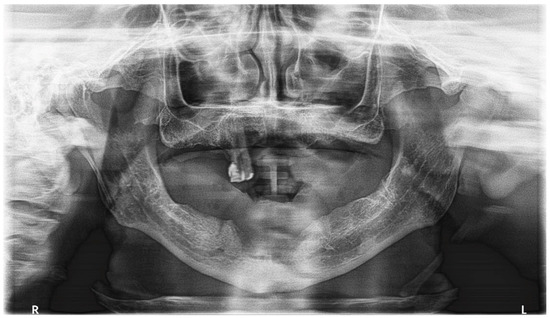

2.4. Diagnostic Assessment

2.5. Therapeutic Intervention